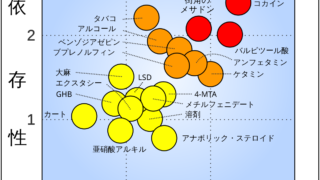

なんGタバコの依存度、ガチでヤバすぎるwwwwww【画像】